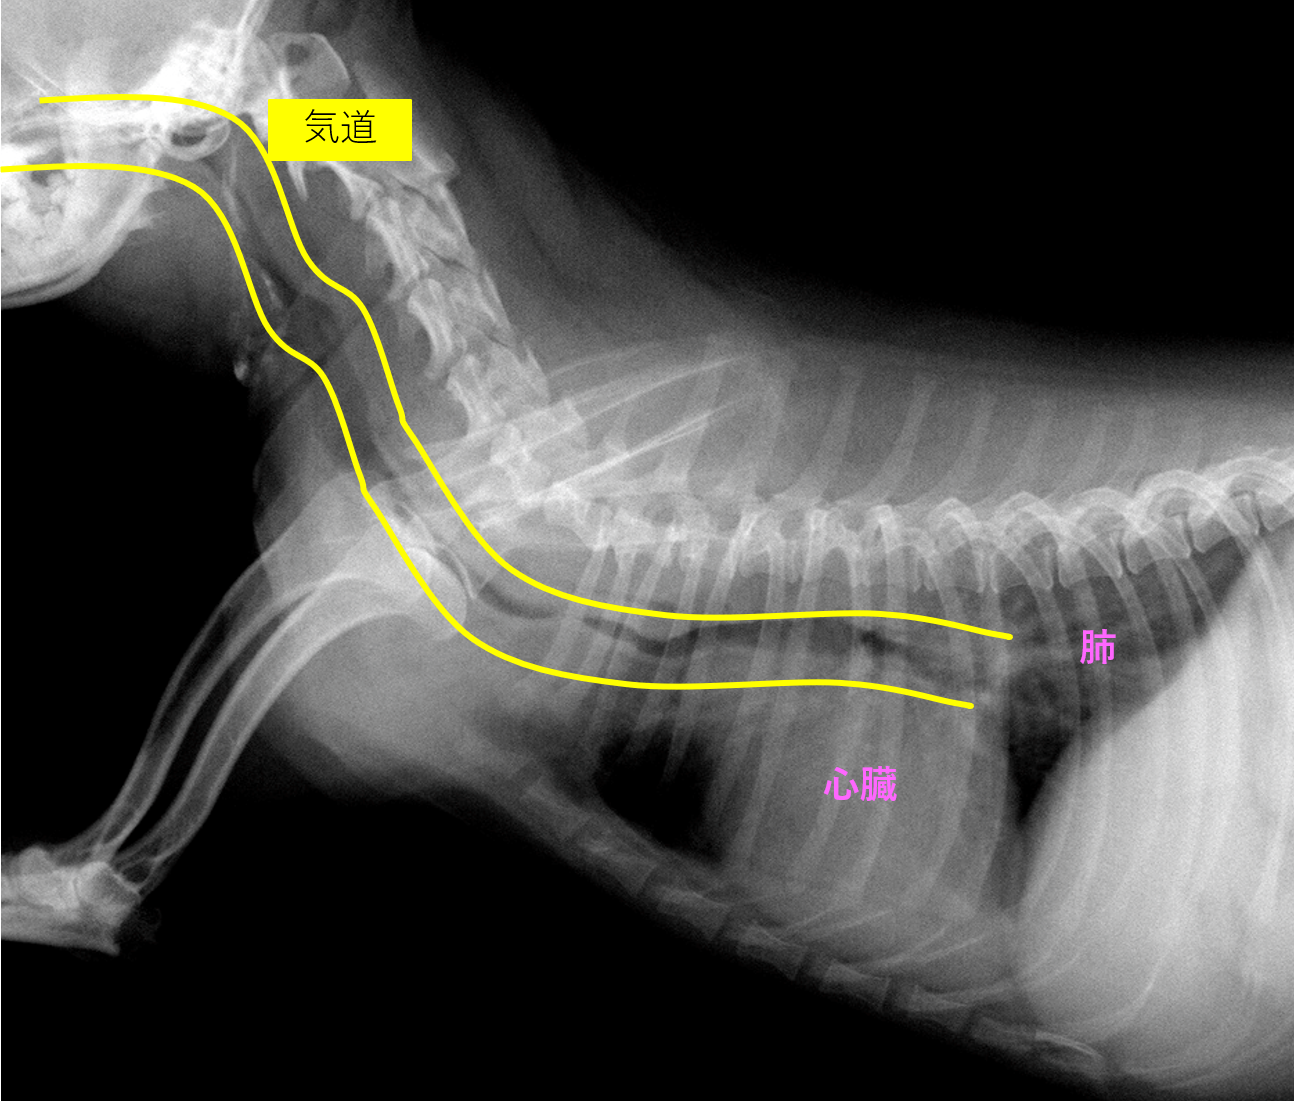

犬 気管支拡張剤 テオドール 副作用- 犬の気管支炎 レントゲン撮って見せてもらうと気管が白くなってる 気管支炎らしい ウイルスや細菌、アレルギーなど色々な原因がありなぜ急に気管支炎にかかったか詳しく分かりま不調を抱えた犬の症状・原因について 気管とは喉の奥から肺にかけての空気の通り道のことです。 気管はやがて枝分かれしていき、この枝分かれした部分から先を気管支と言います。 気管支狭窄